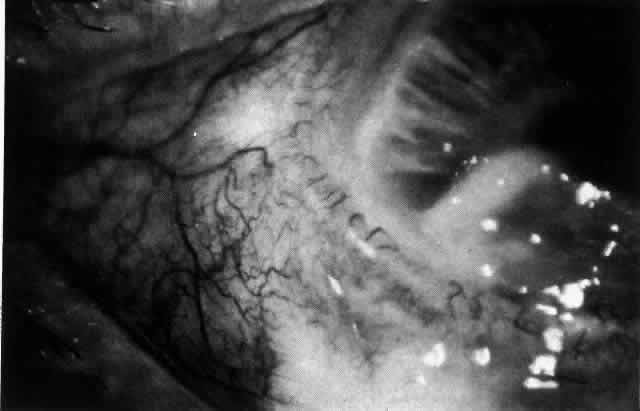

ARTERIAL PHASE Anterior Episcleral Arterial Circle The anterior ciliary arteries run radially toward the limbus within Tenon's capsule, giving few, if any, branches until they reach the anterior part of the globe. Their positions are very variable, and they do not always follow the rectus muscles. They bifurcate 2 to 5 mm behind the limbus, and each division runs forward and circumferentially to anastomose with a branch from an adjacent artery. This results in an anterior episcleral arterial circle (Figs. 3 through 5). The divisions of the anterior ciliary arteries are typically superficial at their origins but run deeper at their anastomoses. They occasionally dip too deep to be seen in fluorescein angiograms (Fig. 6).

From the anterior episcleral arterial circle, four distinct circulations are supplied: episcleral, anterior conjunctival, limbal, and iris. Episcleral Circulation Immediately after their origin by bifurcation of the anterior ciliary arteries, the contributions to the anterior episcleral circle divide again to give recurrent branches that run posteriorly and subdivide to form a netlike episcleral plexus (see Fig. 5; Fig.7). The variability of the positioning of the anterior ciliary arteries inevitably leaves large areas of episclera far from such an arterial supply (see Figs. 4, 6, and 7). These areas receive other posterior branches from the episcleral circle. Where the circle runs deep within the sclera, such branches appear as isolated perforating vessels (see Fig. 6). They fill very shortly after the episcleral circle, and they also divide repeatedly as they run posteriorly.